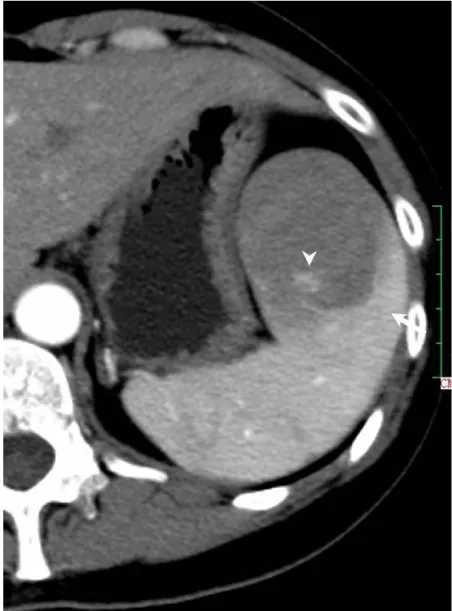

Solitary well-circumscribed masses were detected in all the five patients by ultrasound. One mass was of hypoecho, while the remaining masses were of hyperecho with posterior enhancement (Figure 1A). The maximum diameter ranged from 3.0 cm to 9.0 cm. At CT scanning, two masses appeared as hypodense (Figure 1B) and one was isodense (Figure 2A) to the normal spleenic parenchyma. In the two patients who received MR imaging, masses were isointensity at T1 weighted images (Figure 3A) and hypointensity with scattered sign void spots at T2 weighted images (Figure 3B). After intravenous injection of the contrast materials, all the five masses presented circle enhancement at arterial phase (Figure 3C and Figure 4A), while peripheral enhanced node was noted in one mass (Figure 2B). The circle enhancement persisted and radical line enhancement were observed at portal vein phase in 3 cases (Figure 1C) and progressive filling in was seen in two cases (Figure 2C). At delay phase of MR imaging, one lesion showed obvious enhancement with stellate low signal scar in the center comparing with surrounding splenic parenchyma (Figure 3D), while the other demonstrated central and circle enhancement to form a spoke-like appearance (Figure 4B). At delay enhanced CT scanning, two masses were isoattenuation to the surrounding splenic parenchyma (Figure 2D) and one lesion kept as hypoattenuation but with radial enhanced lines and enhanced circle to form a spoke-like appearance.

At pathological examination, all the masses were well demarcated on gross cut surface. A central stellate scar with peripheral interspersed dark brown nodules and the whitish intervening fibrous bands was noted to form spoke-like appearance (Figure 3E), which was well correlated with CT and MR imaging findings at enhancement. Microscopically, these angiomatoid nodules were surrounded by dense concentric collagen fibrous stroma and dispersed stromal cells with oval-to-spindle nuclei and scanty cytoplasm (Figure 3F). The abunden fibrous stroma may result in hypointensity at T2 weighted MR images. Hemosiderin was noted in the angiomatoid nodules (Figure 3G), which might contributed to signal void at T2 weighted MR images.